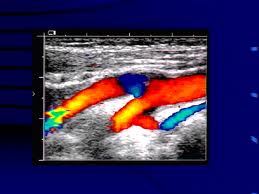

AngiologiaSono patologie estremamente diffuse e pericolose che rappresentano un problema sociale molto rilevante. Sono le malattie vascolari alle quali è stata dedicata un’intensa giornata di studio, ma anche di confronto e di aggiornamento, che si è svolta nell’auditorium del Ce.S.I. (Centro di Eccellenza Studi sull’Invecchiamento) dell’università d’Annunzio, a Chieti Scalo, nel corso del 2° Congresso Regionale della SIAPAV, la Società Italiana di Angiologia e Patologia Vascolare. Si è parlato tanto di malattie, come l’arteriopatia periferica ed il tromboembolismo venoso, che hanno tanti fattori di rischio considerati tra i problemi più diffusi delle società avanzate; su tutti, sono stati messi in evidenza dai relatori nazionali e locali, il fumo, il diabete, l’obesità, l’iperlipidemia e l’ipertensione.